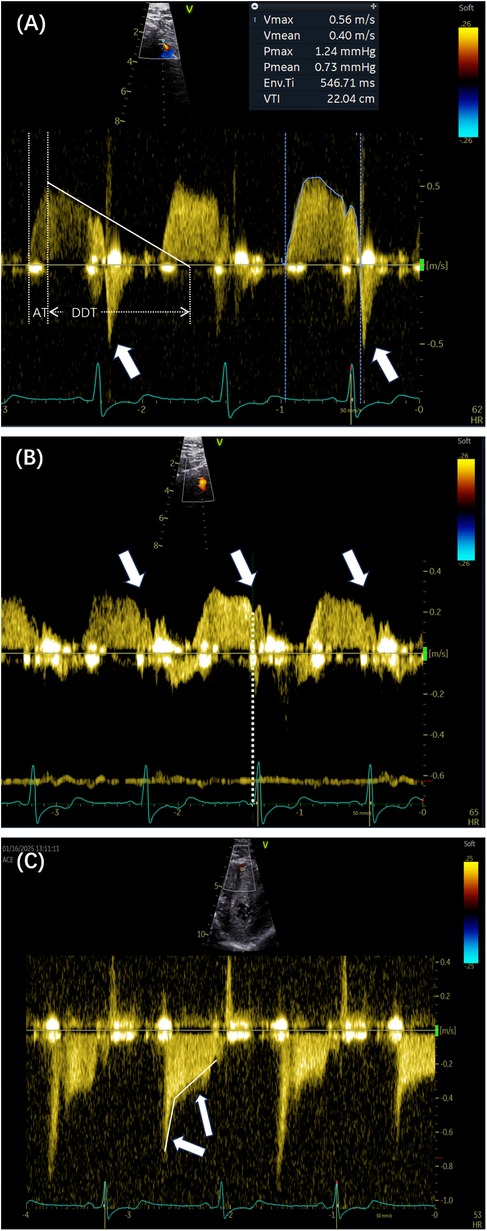

Previous studies have indicated that resting coronary velocity is higher when CFVR is lower. Several retrospective studies have highlighted the prognostic significance of coronary velocity, with prospective observations gradually complementing these findings. In a prospective study involving 747 patients, Zagatina et al. (5) evaluated the proximal left-sided artery segment and middle segments, with a resting coronary velocity exceeding 64–67 cm/s serving as the cutoff for predicting death, myocardial infarction, and MACEs. Additionally, the value of 65 cm/s stratified the patients into the three following groups: high risk of death or myocardial infarction at the incidence of 5.6% per year, as classified by increased velocity in the proximal left-sided artery segments; moderate risk at 2.3% per year, as stratified by increased velocity in the middle segments; and low risk at 0.3% per year, as characterized by any segment maximal velocity below 65 cm/s. Subgroup analyses of patients with known CAD, suspected CAD, arterial hypertension, valvular disease, and chest pain with unknown reason also supported the positive correlation between higher coronary velocity and increased incidence of death, myocardial infarction, and MACEs (5). A resting coronary flow velocity cutoff of 32 cm/s has also been associated with worse outcomes in patients with chronic coronary syndromes and preserved left ventricular ejection fraction (LVEF), adding incremental prognostic value to CFVR assessments (19). The emphasis on resting flow velocity is justified, as it should not merely serve as an auxiliary parameter for CFVR measurement. Increased baseline velocity may mechanistically contribute to reduced CFVR. Figure 3 illustrates high resting velocity coexisting with reduced CFVR.

Figure 3

(A) The distal LAD arterial flow velocity at rest was 0.58 m/s. (B) The distal LAD arterial flow velocity under vasodilator-induced hyperemia was 0.88 m/s. The coronary flow velocity reserve was 1.58. LAD, left anterior descending.